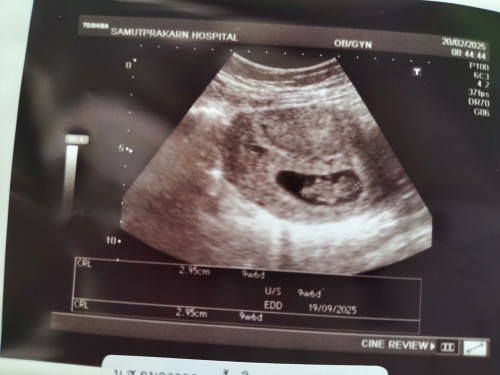

ซาวด์ล่าสุดน้องได้10+5วีคแล้วค่ะ แม่ยังไม่แพ้ท้องค่ะ น้ำหนักแม่ขึ้นมา 2โล ภายใน1เดือน ถือว่าเยอะมั้ยคะ 🥰😄